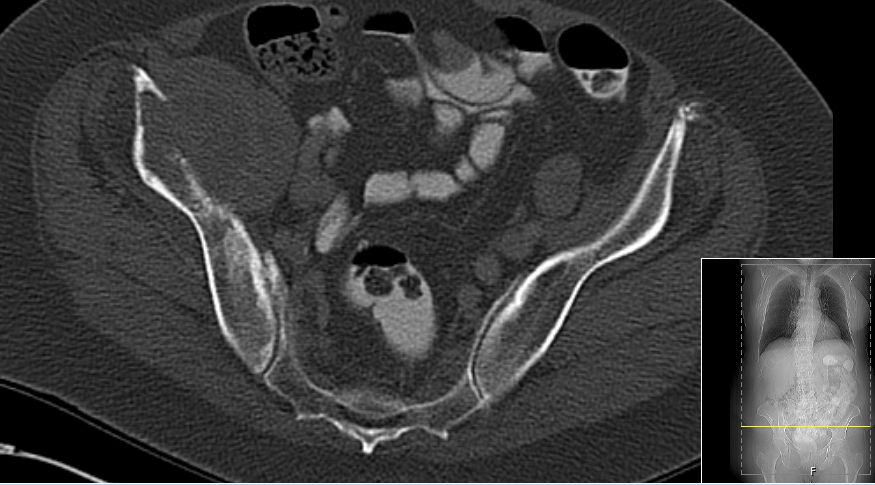

CT: 6,4 x 4 cm große kapsulierte tumoröse Raumforderung in der Fossa iliaca rechts mit knöchernen Destruktion des Os

ileum. Dichte bis 20 HEs.![]() |